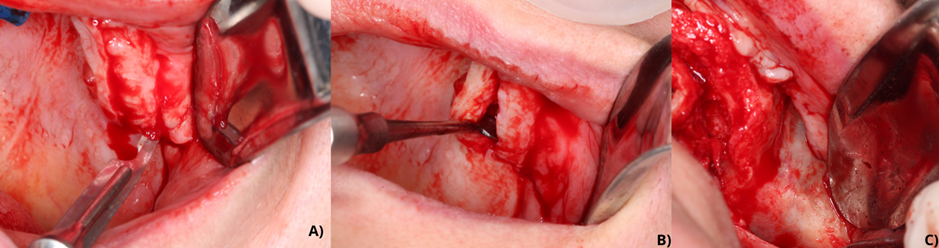

Foi feita anestesia de bloqueio do nervo infraorbitário, nasopalatino, palatino maior, alveolar anterior, alveolar médio e alveolar posterior com solução de articaína com epinefrina. Após bloqueio anestésico, iniciou-se o processo de incisão crestal em todo rebordo alveolar remanescente de maxila. Foi feita também duas incisões relaxantes de região crestal até o fundo de vestíbulo, aproximadamente em região de segundo pré-molar de ambos os quadrantes superiores. Seguindo a sequência cirúrgica, foi feito descolamento de tecido gengival, periósteo e tecidos adjacentes para visualização de campo cirúrgico e identificação das estruturas anatômicas, pilar canino e parte do osso zigomático (Figura 4).

Com auxílio de lápis de carbono estéril foram feitas marcações para identificação das estruturas anatômicas de pilar canino em maxila, processo maxilar do osso zigomático e face lateral do osso zigomático e para posterior posicionamento de instalação dos implantes. No decorrer do ato cirúrgico houve a necessidade de realizar osteotomia em crista alveolar do primeiro quadrante em maxila, com auxílio da broca Maxcut revestida de zircônia, utilizada em peça reta com irrigação no motor de baixa rotação para melhor acesso e posicionamento da broca fresagem para instalação de implante na região de zigomático direito.